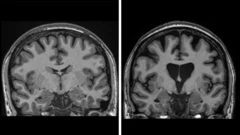

Можно ли победить болезнь Альцгеймера? Ученые считают, что сделают это через 5-10 лет

Могут ли распространенные вирусы увеличить риск развития болезни Альцгеймера — и одновременно стать лекарством от нее